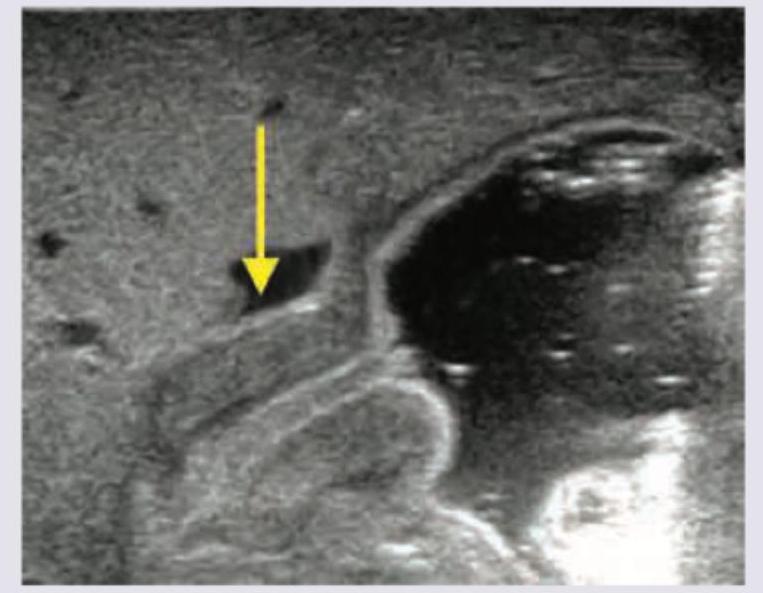

Neonate is brought at 3 weeks of age, with projectile vomiting. USG was performed and is shown below. When can the abdominal mass in this condition be best palpated?

Explanation: ***During feeding*** - In **hypertrophic pyloric stenosis**, the characteristic **"olive" mass** formed by the thickened pylorus is most easily palpable **during feeding or immediately after vomiting**. - During this time, the infant’s abdominal muscles are relaxed, making palpation of the mass in the **epigastrium (right upper quadrant)** more successful. *In umbilical area* - The umbilical area is typically where **omphaloceles** or **umbilical hernias** are found, not the pyloric mass. - The pylorus is located much higher in the epigastric region, to the right of the midline. *In epigastric area* - While the pyloric mass is located in the **epigastric area**, palpation is more difficult when the infant is crying or agitated. - The question asks when it can be *best* palpated, emphasizing the conditions under which it is most detectable. *In Right upper quadrant* - The pylorus is indeed located in the **right upper quadrant/epigastrium**. - However, the optimal timing for palpation is during feeding or after vomiting, as the infant's abdomen is relaxed at that point.